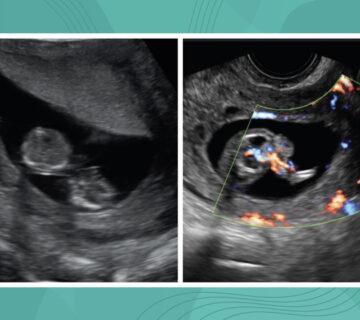

En USA las mujeres con cardiopatías congénitas que se embarazan son menos del 0.1% de las gestantes, pero gracias a los avances tecnológicos, esta cifra se irá incrementando. A pesar de una baja tasa de mortalidad materna, estas pacientes tienen mucho más riesgo de eventos cardiológicos serios (2.8%). Sin embargo, la evidencia reporta que casi la mitad de estas complicaciones son prevenibles, si hay un mejor entendimiento de la fisiología subyacente y el manejo expectante, ambos ayudarían a mejorar los resultados maternos y fetales.

- El riesgo de transmisión de una cardiopatía congénita varía del 3-7%, riesgo ligeramente mayor cuando la madre es la afectada. A pesar de que la mayoría de malformaciones cardíacas congénitas no están asociadas a un síndrome o herencia mendeliana asociada a gen único (Síndrome Holt-Oram), se debe tener cuidado en la toma de datos de historia clínica personal e historia familiar por manifestaciones extracardíacas que podrían ayudar a identificar más síndromes como Noonan o Di George, los cuales podrían tener patrones de herencia bien definidos.

- Las complicaciones neonatales son más frecuentes que en la población general y están altamente relacionadas con el estatus cardíaco de base (pobre estatus funcional, cianosis, válvulas mecánicas, entre otras).